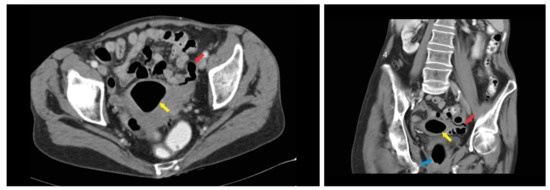

2. Case Report